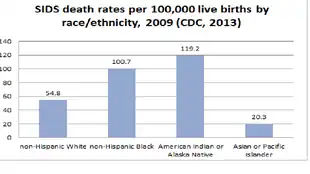

Race

In 2013, there are persistent disparities in SIDS deaths among racial and ethnic groups in the U.S. In 2009, the rates of death range from 20.3 per 100,000 live births for Asian/Pacific Islander to 119.2 per 100,000 live births for Native Americans/Alaska Native. African American infants have a 24% greater risk of having a SIDS related death[81] and experience a 2.5 greater incidence of SIDS than in Caucasian infants.[82] Rates are per 100,000 live births and enable more accurate comparison across groups of different total population size.

Research suggests that factors which contribute more directly to SIDS risk—maternal age, exposure to smoking, safe sleep practices, etc.—vary by racial and ethnic group and therefore risk exposure also varies by these groups.[2] Risk factors associated with prone sleeping patterns of African American families include mother's age, household poverty index, rural/urban status of residence, and infant's age. More than 50% of African American infants were placed in non-recommended sleeping positions according to a study completed in South Carolina.[83] Cultural factors can be protective as well as problematic.[84]

The rate per 1000 births varies in different ethnic groups in the United States:[26][85]

- Central Americans and South Americans: 0.20

- Asian/Pacific Islanders: 0.28

- Mexicans: 0.24

- Puerto Ricans: 0.53

- Whites: 0.51

- African Americans: 1.08

- Native American: 1.24